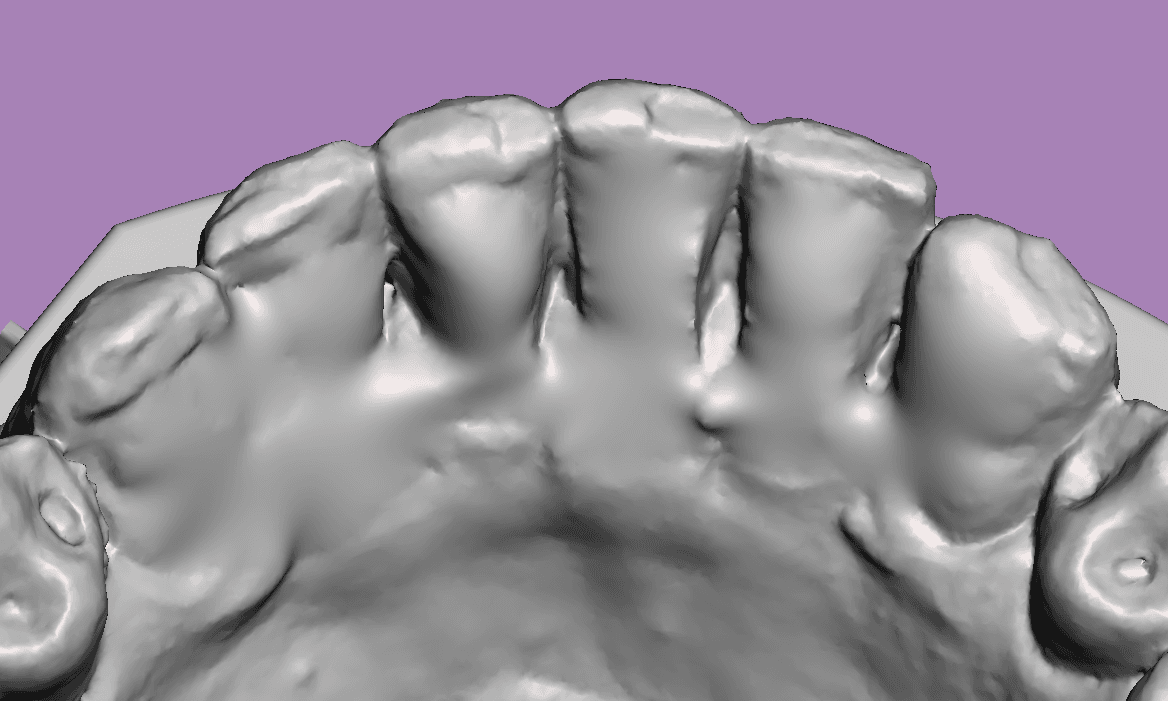

Escaneamento sem contenção

Escaneamento com contenção removida virtualmente

Quanto maior a precisão da cópia do nosso escaner maior será a acurácia da movimentação planejada.